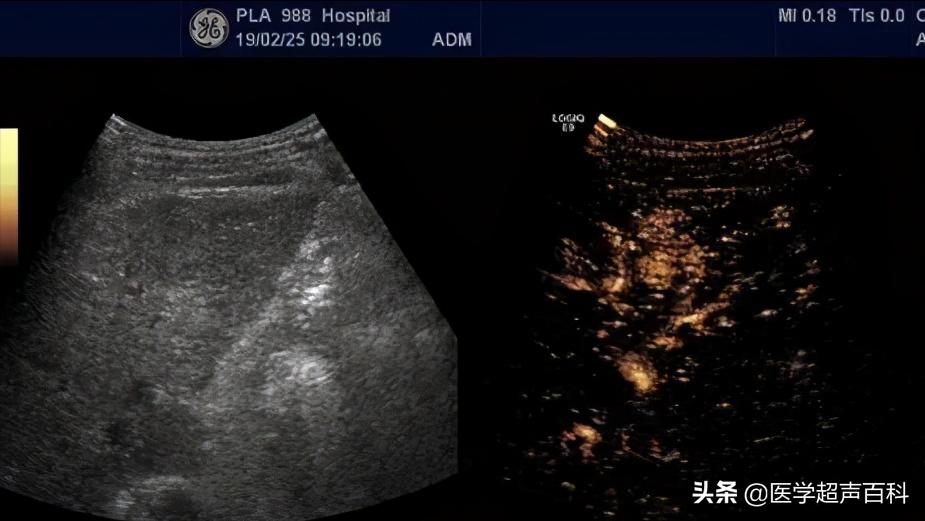

异常回声区

正常肝实质,回声呈较低的细小光点,分布均匀。如果肝上有占位性肿块,B超会提示异常回声区。如果肝内回声不均,提示可能脂肪肝、肝纤维化;如果有强回声区,提示肝内可能有胆管结石、钙化灶,一般无大碍;如果强回声同时血管很丰富,则血管瘤可能性大;如果提示无回声区,则肝囊肿可能性大;如果提示肝内低回声,其内回声不均匀,边界不清楚,可能与肿瘤等相关;如果提示多发低回声区,要怀疑是否是消化道肿瘤肝转移。一旦发现异常回声,要到大医院复查彩超或是进一步做增强CT或核磁,以了解包块的性质。

早期微小肝癌在 1-2cm

慢性肝病要求三个月查一次超声,目的一是了解肝质地情况,更重要的是监测早期肝癌的出现,早期微小肝癌在 1-2cm 就已被能发现,对早期治疗意义重大,如在检查中发现了异常结节,经超声造影甚至活检,可以很快确定是否是肝癌,早期微小肝癌不管是手术还是介入,疗效都相当不错,存活 5 年、8 年已是很常见,甚至可完全治愈。